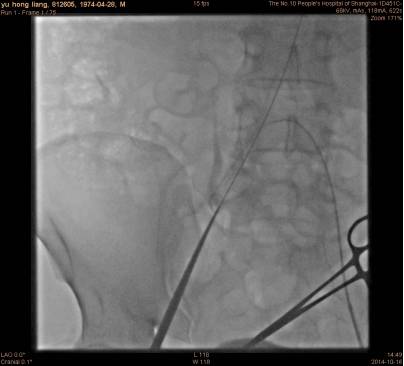

穿刺左侧股动脉,置入6F鞘管,行左心室造影;

穿刺右侧股动脉,使用血管缝合系统(Preclose)预先埋缝线;

右侧股动脉置入16F鞘管,6FPigtail导管进入左心室,沿猪尾巴置入强生cordis加硬导丝;

沿导丝将16F指引导管置入心尖部;

沿指引导管置入Parachute,左室造影与心超检查位置。

手术过程左心室造影: